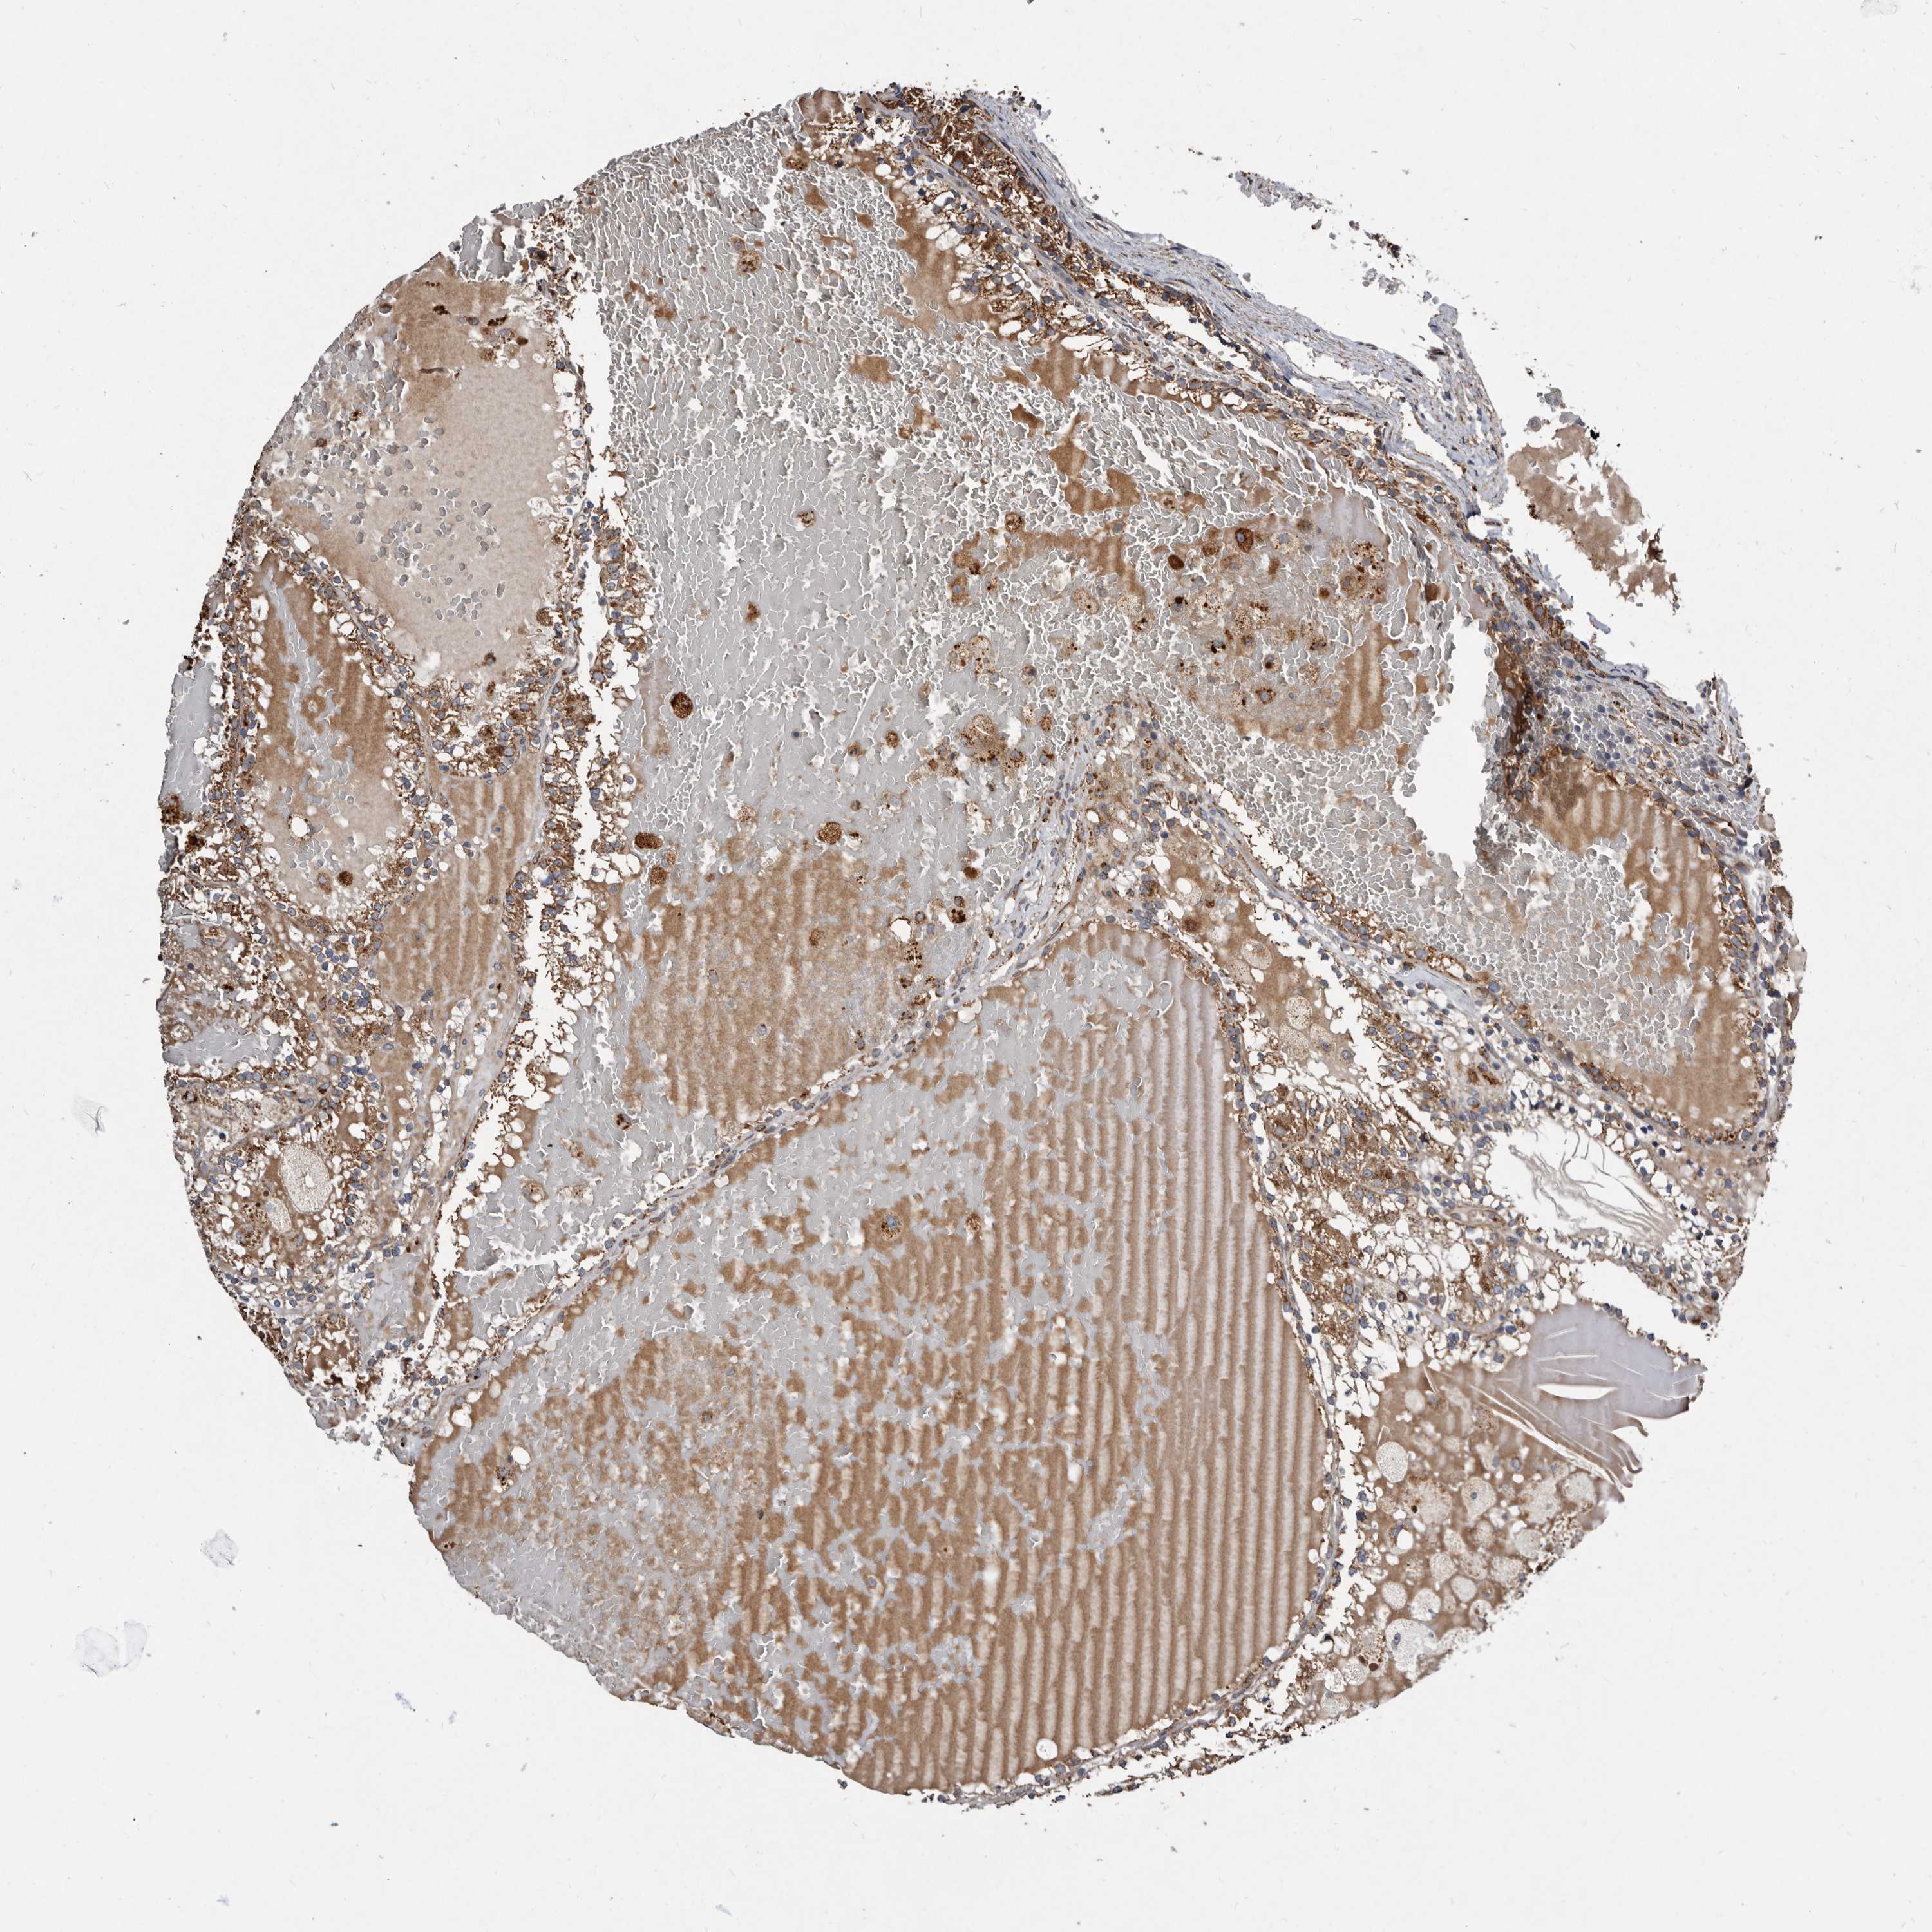

KIDNEY RENAL CLEAR CELL CARCINOMA (VALIDATION) - Interactive survival scatter ploti

The Survival Scatter plot shows the clinical status (i.e. dead or alive) for all individuals in the patient cohort, based on the same data that underlies the corresponding Kaplan-Meier plots. Patients that are alive at last time for follow-up are shown in blue and patients who have died during the study are shown in red.

The x-axis shows the expression levels (FPKM) of the investigated gene in the tumor tissue at the time of diagnosis. The y-axis shows the follow-up time after diagnosis (years). Both axes are complimented with kernel density curves demonstrating the data density over the axes. The top density plot shows the expression levels (FPKM) distribution among dead (red) and alive patients (blue). The right density plot shows the data density of the survived years of dead patients with high and low expression levels respectively, stratified using the cutoff indicated by the vertical dashed line through the Survival Scatter plot. This cutoff is automatically defined based on the FPKM cutoff that minimizes the p-score. The cutoff can be changed by dragging the vertical line or by entering a cutoff value in the square labeled "Current cut-off".

Under the Survival Scatter plot the p-score landscape (black curve; left axis) is shown together with dead median separation (red curve; right axis). Dead median separation is the difference in median mRNA expression between patients who have died with high and low expression, respectively. It is calculated as follows: median FPKM expression of dead patients with high expression - median FPKM expression of dead patients with low expression. This is intended to aid the user in visually exploring custom cutoffs and the associated p-scores and dead median separation.

Individual patient data is displayed and can be filtered by clicking on one or more of the category buttons on the top of the page. Categories describing expression level and patient information include: high, low, alive, dead, female, male and tumor stages. The scale of the x-axis can be toggled between linear and log-scale by clicking on the "x log" button. Mouse-over function shows TCGA ID, patient information and mRNA expression (FPKM) for each patient.

& Survival analysisi

Kaplan-Meier plots summarize results from analysis of correlation between mRNA expression level and patient survival. Patients were divided based on level of expression into one of the two groups "low" (under cut off) or "high" (over cut off). X-axis shows time for survival (years) and y-axis shows the probability of survival, where 1.0 corresponds to 100 percent.

CTSA is not prognostic in Kidney Renal Clear Cell Carcinoma (validation)

Best expression cut offi

Based on the FPKM value of each gene, patients were classified into two groups and association between prognosis (survival) and gene expression (FPKM) was examined. The best expression cut-off refers the FPKM value that yields maximal difference with regard to survival between the two groups at the lowest log-rank P-value. Best expression cut-off was selected based on survival analysis .

When clicking on this number, the vertical dashed line indicating cut-off, the interactive survival plot, and the Kaplan-Meier curve will be adjusted to show results based on the best expression cut-off.

: 197.86

P scorei

Log-rank P value for Kaplan-Meier plot showing results from analysis of correlation between mRNA expression level and patient survival.

N/A

5-year survival highi

5-year survival for patients with higher expression than the expression cutoff.

For melanoma and glioma, 3-year survival is shown.

5-year survival lowi

5-year survival for patients with lower expression than the expression cutoff.

TCGA RNA samplesi

RNA-seq data is reported as average FPKM (number Fragments Per Kilobase of exon per Million reads), generated by the The Cancer Genome Atlas (TCGA) .

Normal distribution across the dataset is visualized with box plots, shown as median and 25th and 75th percentiles. Points are displayed as outliers if they are above or below 1.5 times the interquartile range. FPKM values of the individual samples are presented next to the box plot.

Average pTPM 217.6

Number of samples 100